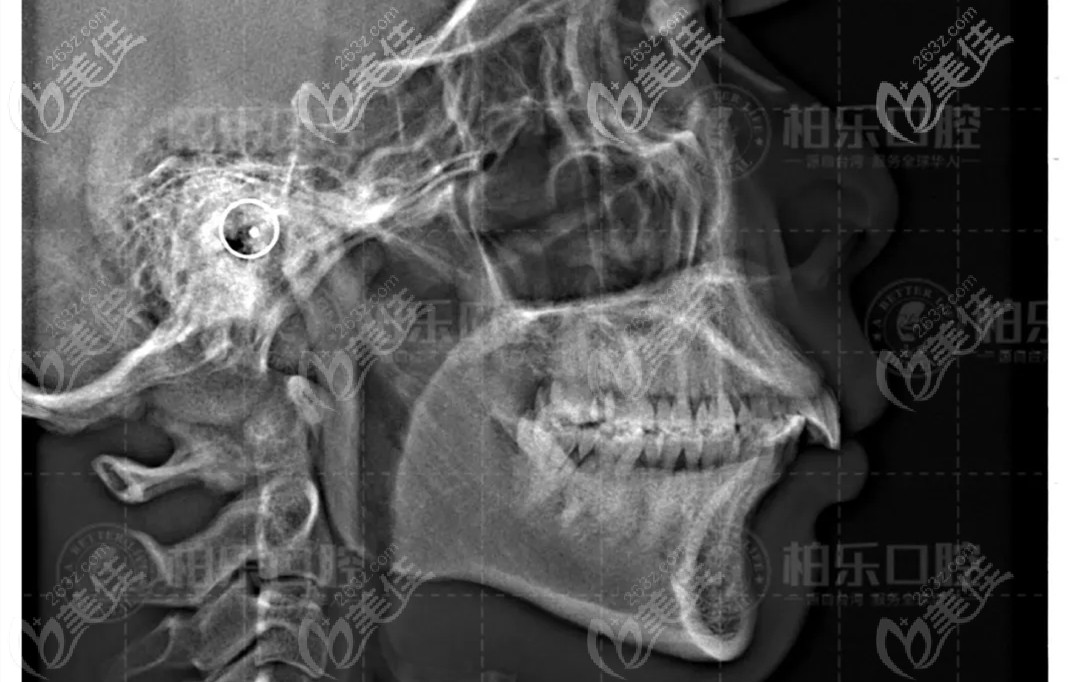

在朋友的推薦下來到了南寧柏樂口腔,拍片經(jīng)過醫(yī)生面診后,才解開了自己心中的謎,原來我的嘴突和下巴短是由于深覆合深覆蓋導(dǎo)致的(這個專 業(yè)術(shù)語之前都沒有聽說過),也就是大家俗稱的天包地,咬牙時上前牙切緣蓋過下前牙牙冠長度 1/3 以上或下前牙咬合于上前牙舌側(cè) 1/3 以上。

下定決心之后,醫(yī)生開始和我聊設(shè)計方案,采用的是推磨牙向后的方式來調(diào)整磨牙關(guān)系,協(xié)調(diào)前牙覆合覆蓋;24歲的我正是在乎美觀性的時候,而且生活和工作中要經(jīng)常和別人交流,所以我選擇了摘戴方便,透明隱適美矯正器(丟三落四的人不建議選擇)。

總的來說,就是看到自己現(xiàn)在一點(diǎn)點(diǎn)的變化,感覺挺值得的,隱適美推磨牙向后一點(diǎn)也不后悔;所以,過來人告訴你,矯正一定要趁早,而且拍片真的很重要,不拍僅僅憑肉眼看,都不知道自己的問題。